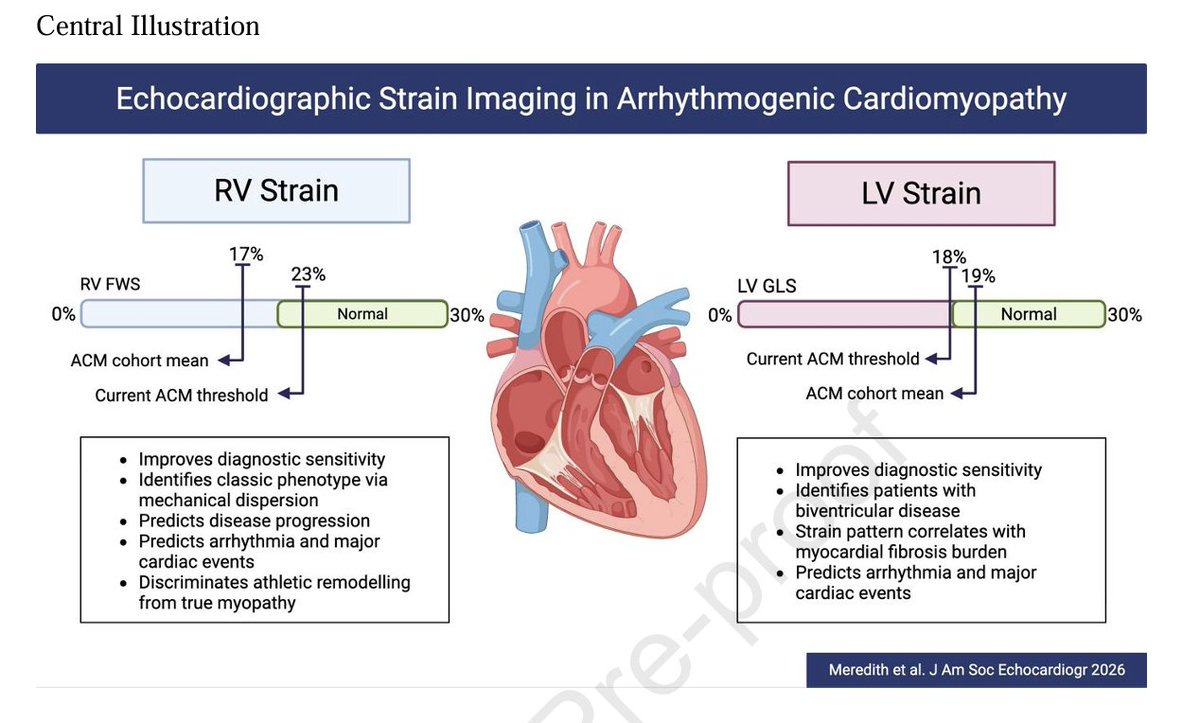

🔴State-of-the-Art in Echocardiographic Strain Imaging of Arrhythmogenic Cardiomyopathy @ASE360 #Cardiology #CardioEd #echofirst #Strain

🔴State-of-the-Art in Echocardiographic Strain Imaging of Arrhythmogenic Cardiomyopathy @ASE360 #Cardiology #CardioEd #echofirst #Strain